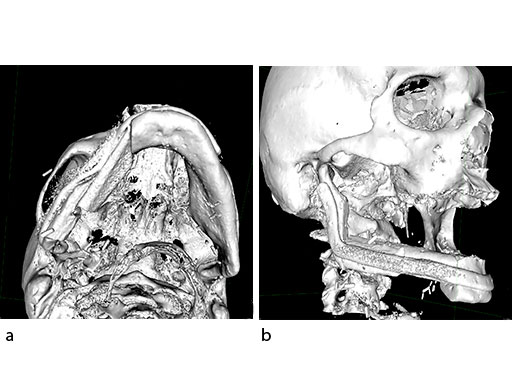

A 58-year-old male patient had oral cancer (T4n0m0) infiltrating the alveolar process and the anterior border of the ascending ramus (Fig 2). The treatment plan involved resection, bilateral neck dissection (levels I to III), and primary mandibular reconstruction with a right osteomyofasciocutaneous fibula flap.

At this stage, future dental implant insertion requires an alveolar process in a lingual shift position. To this end, the anterior segment is aligned with a medial offset. The posterior segment, which replaces the angle/anterior ramus region, is arranged with an overlapping zone. The inner cortex of the posterior segment in the area of intersection is trimmed to keep the restoration within the bounds of the original width of the angle. This results in a sort of "bayonet connection". The basal border of the mandibular body is not built up, since it is not functionally relevant.

With the design of the bony framework being ready, the reconstruction plate is molded to the geometry of the outer surface of the neomandibular division. The plate profile (thickness 2.0 or 2.5 mm) is chosen and the plate screw hole pattern is customized. Relative to the osteotomy sites, the fibular segment configuration, and the adjacent native bone, the number, position, and angulation (up to 15) of the plate screw holes is specified with respect to overall stability. A defined screw hole position facilitates accessibility for screw insertion and avoids interference with nerves, tooth roots, osteotomy interfaces, and existing/future implants.